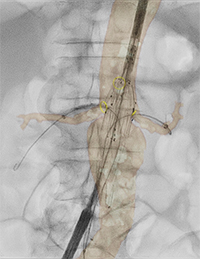

腹部大動脈瘤治療臨床症例2*3 |

*3 出典:Prof. Dr. M. Schermerhorn, BIDMC, Boston, USA, Endovascular Repair of Juxtarenal Abdominal Aortic Aneurysm